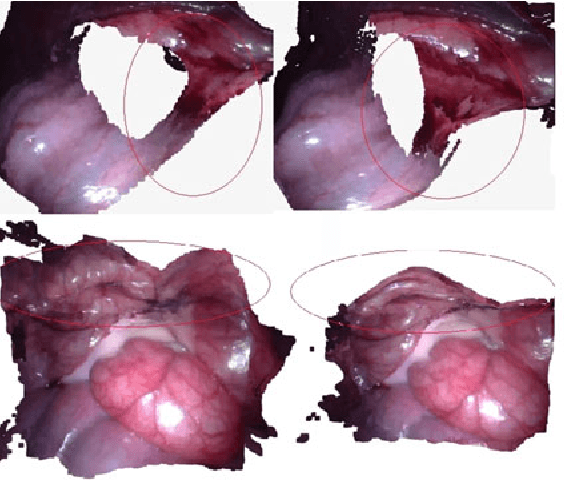

In minimal invasive surgery, it is important to rebuild and visualize the latest deformed shape of soft-tissue surfaces to mitigate tissue damages. This paper proposes an innovative Simultaneous Localization and Mapping (SLAM) algorithm for deformable dense reconstruction of surfaces using a sequence of images from a stereoscope. We introduce a warping field based on the Embedded Deformation (ED) nodes with 3D shapes recovered from consecutive pairs of stereo images. The warping field is estimated by deforming the last updated model to the current live model. Our SLAM system can: (1) Incrementally build a live model by progressively fusing new observations with vivid accurate texture. (2) Estimate the deformed shape of unobserved region with the principle As-Rigid-As-Possible. (3) Show the consecutive shape of models. (4) Estimate the current relative pose between the soft-tissue and the scope. In-vivo experiments with publicly available datasets demonstrate that the 3D models can be incrementally built for different soft-tissues with different deformations from sequences of stereo images obtained by laparoscopes. Results show the potential clinical application of our SLAM system for providing surgeon useful shape and texture information in minimal invasive surgery.